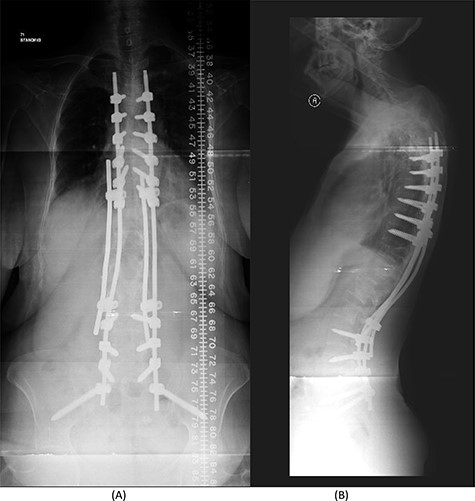

Over a year after the surgical procedure with the bridging technique, the patient presented with a new-onset lower back pain after hearing a crack. X-ray showed bilateral rod fractures and the CT scan showed re-ossification of the involved levels (T11–L3; Fig. 5). An MRI showed complete recovery of the infection without cord compression (Fig. 6). At this stage, we elected to proceed with a revised surgical intervention that involved adding bilateral pedicle screws at the re-ossified vertebrae (T11, T12, L2 and L3). The patient tolerated the surgery well and had a normal neurological examination postoperatively. CT scan post revision demonstrated fixation of T5 to S2 alar-iliac with a well-fixed construct. CRP level upon discharge was 7 mg/l and procalcitonin was <0.02 ng/ml. The patient was recovering well at follow up 1 year later (Fig. 7).

(A) AP lumbar spine X-ray demonstrating final fixation from T5-S2-alar-iliac screws. (B) Lateral spine X-ray.

The patient underwent a revised form of posterior spinal fixation from T5 to S2 using a bridging technique and double rods on each side to allow healing and re-ossification of the vertebra with removal of the screws in T11–L3. Due to the instability of the bridging technique, the rods were broken and posterior fixation was deemed a failure. The patient underwent a revision of fixation with insertion of pedicle screws in all levels and a single rod on each side (Fig. 7). In this stage, complete eradication of the infection was achieved and there was no collection.